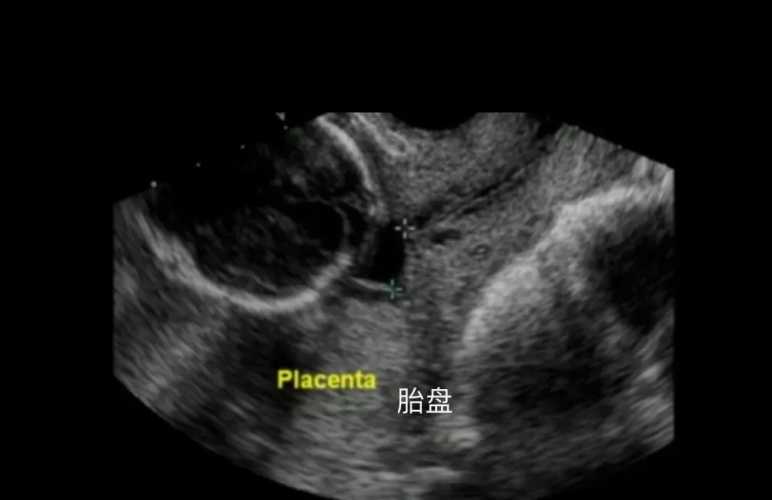

剖腹产胎盘厚是怎么回事

剖腹产胎盘厚是咋回事?这和孕期激素变化、胎盘自身发育还有一些合并情况有关。

孕期激素会影响胎盘生长,有些宝妈身体里激素波动大,胎盘就可能长得厚些。还有胎盘自己发育的情况,比如局部增生也会让胎盘变厚。我之前有个姐妹,产检时发现胎盘厚,后来查是孕期血糖稍微高了点,胎盘为了给宝宝供营养,就跟着增厚了。

不过也别太慌,医生会看胎盘功能、宝宝发育这些情况。要是胎盘厚但功能正常,宝宝也没异常,大多不用太担心;但要是有胎盘早剥这些风险,就得听医生安排啦。